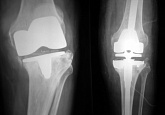

Endoprothetik des Kniegelenks

In den späten Stadien der Arthrose des Knies durch eine ausgeprägte Begrenzung der Bewegung begleitet, konstant starke Schmerzen, körperliche Unversehrtheit Verformung bis zur Genesung der einzige Weg ist der Ersatz des betroffenen Gelenks für eine künstliche - Endoprothetik.

Diese Methode ermöglicht es Ihnen, die richtige Form des Gliedes, eine vollständige Palette von Bewegung im Gelenke, zu entlasten ständige Schmerzen und Knirschen bei Bewegung und als Ergebnis wieder herzustellen, signifikant dem Patienten Lebensqualität zu verbessern.

Im Folgenden sind Röntgenaufnahmen und Fotografien, die die Strecke der Bewegung in der betroffenen Gelenke vor und nach der Operation veranschaulichen.